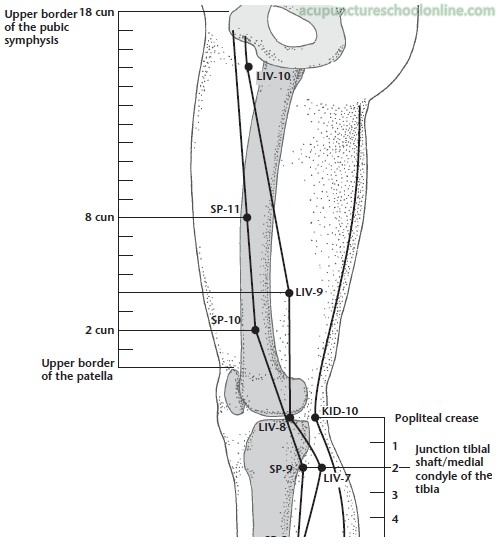

3 cun inferior to Qichong St-30 (2 cun from the midline level with the superior border of the symphysis pubis, Qugu Ren-2) on the anterior border of m. adductor longus.